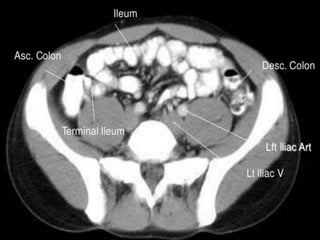

Small Intestine

 The body’s major digestive organ

 Site of nutrient absorption into the blood

 Muscular tube extending from the

pyloric sphincter to the ileocecal valve

 Suspended from the posterior

abdominal wall by the mesentery

Subdivisions of the Small Intestine

 Duodenum(25cm)

Attached to the stomach

Curves around the head of the pancreas

Fixed retroperitoneal structure

 Jejunum (2.5m)

Attaches anteriorly to the duodenum

 Ileum (3.5m)

Extends from jejunum to large intestine

Cecum – pocket at proximal end with

Appendix

Colon

Ascending colon - on right, between

cecum and right colic flexure

Transverse colon - horizontal portion

Descending colon - left side, between

left colic flexure and

Sigmoid colon - S bend near the

terminal end

Regions of Large Intestine

Rectum –terminal end is anal canal - ending at the anus - which has internal

involuntary sphincter and external voluntary sphincter